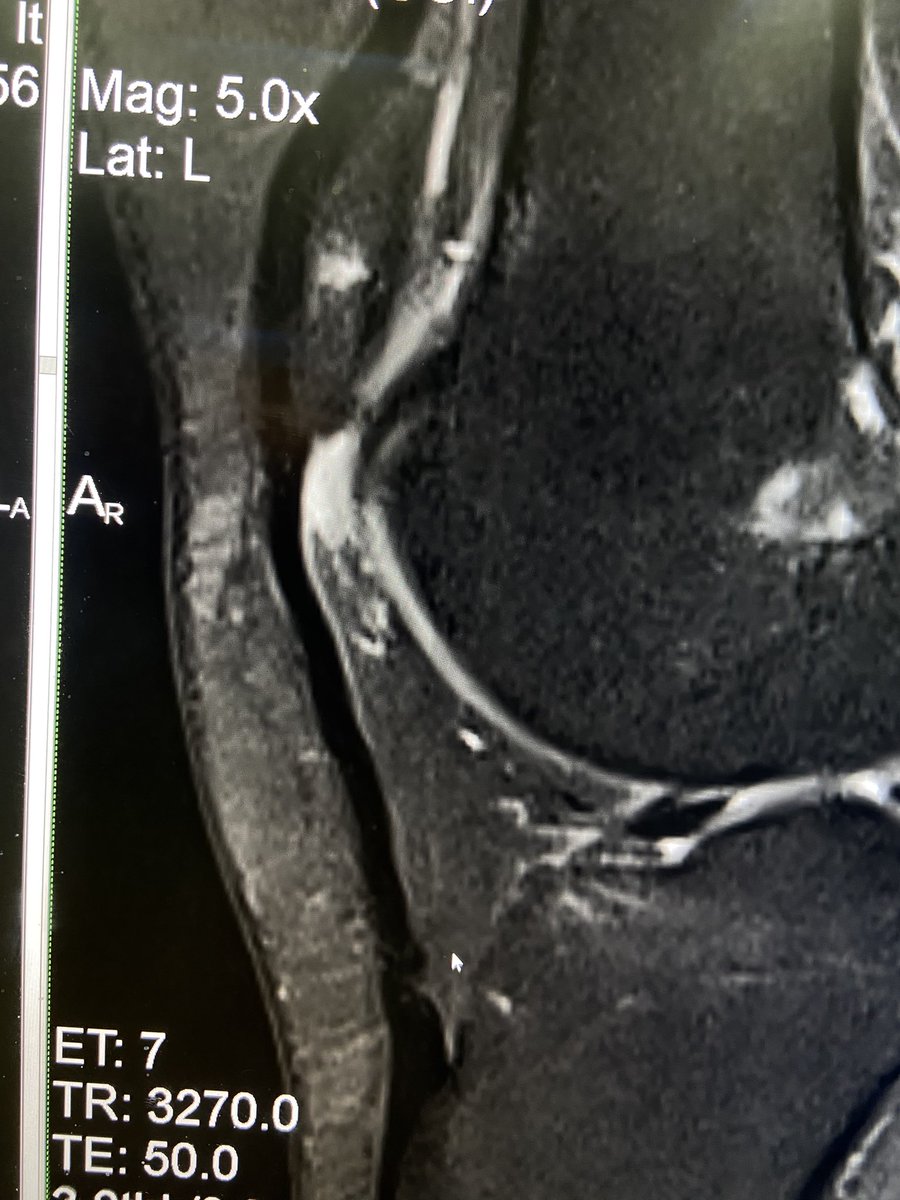

@mskteachingroom @mskradiologyuk @SidThakerMSK @jacja_ @veronica_giotas @PrimeFellowship Migrations of Ca tendinopathy

Spot Diagnosis?